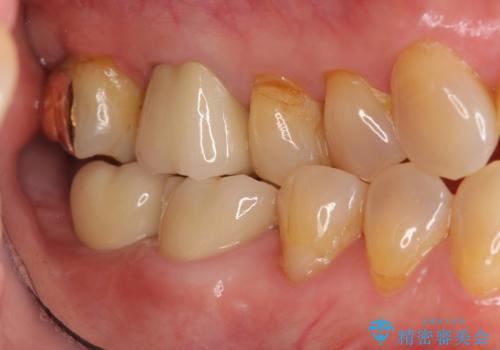

奥歯 インプラントによる機能回復

- 歯を欠損し、噛めないことの治療を希望され来院されました。

インプラントを用いて、しっかりとかめるような治療を計画します。

奥歯のインプラント治療について

最後方臼歯はインプラントを用いることでしっかりと咬合機能を回復することができます。